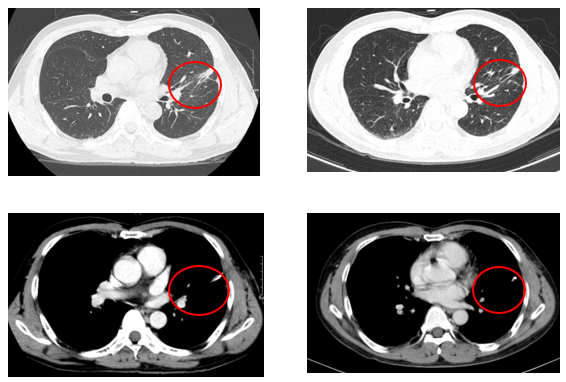

- Chụp cắt lớp vi tính lồng ngực: khối thùy trên phổi trái tỷ trọng tổ chức có phế quản chứa khí, có vôi hóa, 23x25mm, bờ tròn

Hình 1: Hình ảnh chụp cắt lớp vi tính lồng ngực: hình ảnh u thùy trên phổi trái

Chụp cắt lớp vi tính lồng ngực và ổ bụng sau điều trị 3 tháng và 6 tháng:

Hình 5: Hình ảnh chụp cắt lớp vi tính lồng ngực sau điều trị 3 và 6 tháng: vài dải xơ xẹp phổi trái, không phát hiện các tổn thương tái phát, thứ phát